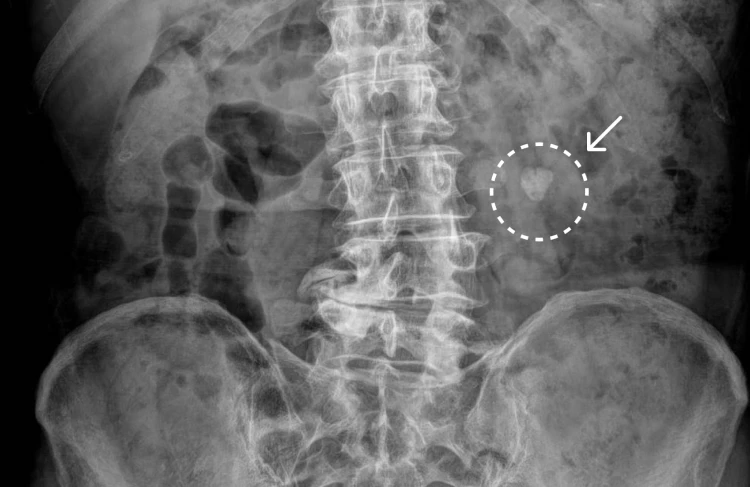

신장 부위에 요로결석이 나타난 엑스레이 이미지, 흰색 원과 화살표로 표시됨